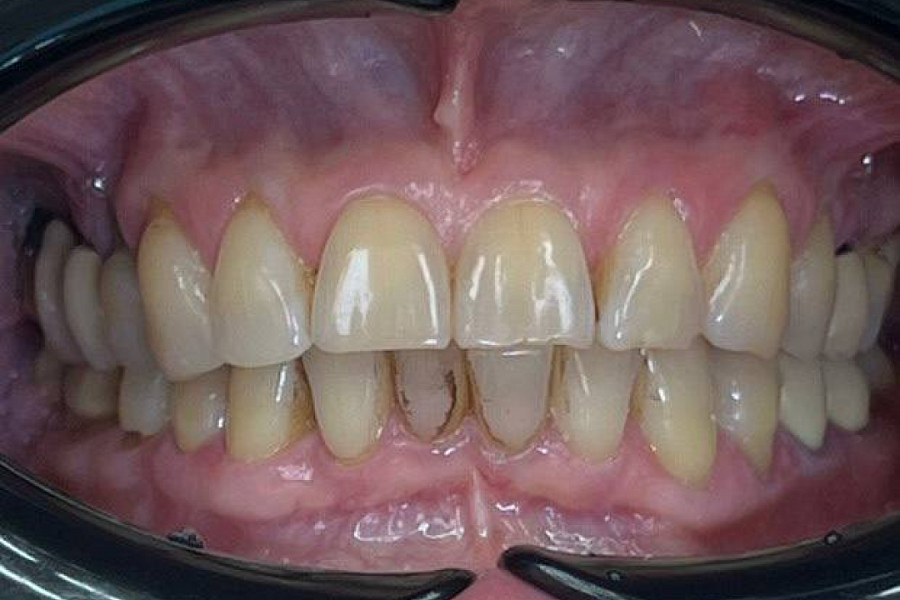

Лечение на ортотике

стираемость зубов

Сделали ортотик, чтобы поставить челюсть в правильное положение.

Далее по плану санация зубов и протезирование в правильной терапевтической позиции ВНЧС. С помощью виниров и коронок будет проведена эстетическая и функциональная реабилитация, получена красивая улыбка и качественное жевание. Лицо подтянется и помолодеет!!

Результат лечения